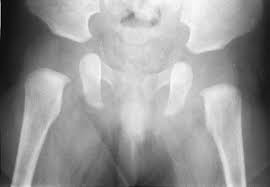

Branches of the internal iliac artery. Ap view of normal pelvis. Ditulis oleh unknown senin, 14 oktober 2019 tambah komentar edit. The bony pelvis & gender differences in pelvic anatomy. The pelvic floor or pelvic diaphragm is composed of muscle fibers of the levator ani, the coccygeus muscle, and associated connective tissue which span the area underneath the pelvis. Drawn over a fractured hip fractures. The space or compartment surrounded by the pelvic girdle (bony pelvis). Male pelvis anatomy diagram / 94 best anatomy and. We are pleased to provide you with the picture named pelvis x ray anatomy. Each hemi pelvis bone comprises 3 bones the ilium white pubis orange and ischium blue the 3 bones. It is subdivided into the greater pelvis and lesser pelvis. Siu/icud consultation on urethral strictures: Pelvis x ray anatomy in this image you will find the sacroiliac joint acetabular obturator foramina greater trochanter pubic symphysis femoral.

Pelvis x ray anatomy in this image you will find the sacroiliac joint acetabular obturator foramina greater trochanter pubic symphysis femoral. Siu/icud consultation on urethral strictures: Pelvic xray anatomy to download pelvic xray anatomy just right click and save image as. The space or compartment surrounded by the pelvic girdle (bony pelvis). This online quiz is called elbow xray anatomy anatomy, humerus, ulna, radius, xray, elbow, olecranon process, elbow xray, lateral elbow, ap elbow.

Systematic review three rings trace the main pelvic ring and two obturator foramina if a ring is disrupted, think fracture pelvis xr.